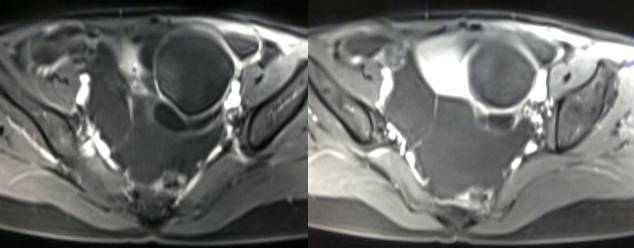

病理结果:黄体血肿

黄体血肿为正常排卵过程中,卵泡层破裂,引起出血,较多的血液潴留在卵泡或黄体腔内形成血肿。

正常黄体直径为15mm左右,以后转变为白体,并在下一个周期的卵泡期自然消退。若黄体内出血量较多,则形成黄体血肿,或称黄体内出血,出血性黄体。黄体血肿多为单侧,一般直径为40mm,偶可达100mm,黄体血肿被吸收后可导致黄体囊肿,较大的血肿破裂时可出现腹腔内出血,剧烈腹痛、少量阴道流血和腹膜刺激征,不易与宫外孕区别。

黄体血肿早期:囊内出血较多时,表现为卵巢内近圆形囊肿,囊壁厚,内壁粗糙。

黄体血肿中期:黄体血肿内血液凝固,部分吸收,囊壁变薄而,内壁光滑。

根据时间不同MR信号也有所不同,TIWI脂肪抑制序列可以鉴别脂肪和出血。